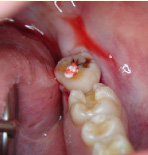

下の写真の一番左は実は治療前の写真です。痛みもなく一見問題なく入っている銀歯も除去してみると中に虫歯が。殺菌作用のある薬を詰めて治療中です。外からは分かりずらい虫歯も多いので定期検診がおすすめです。

- 治療前

- 除去

- 治療中